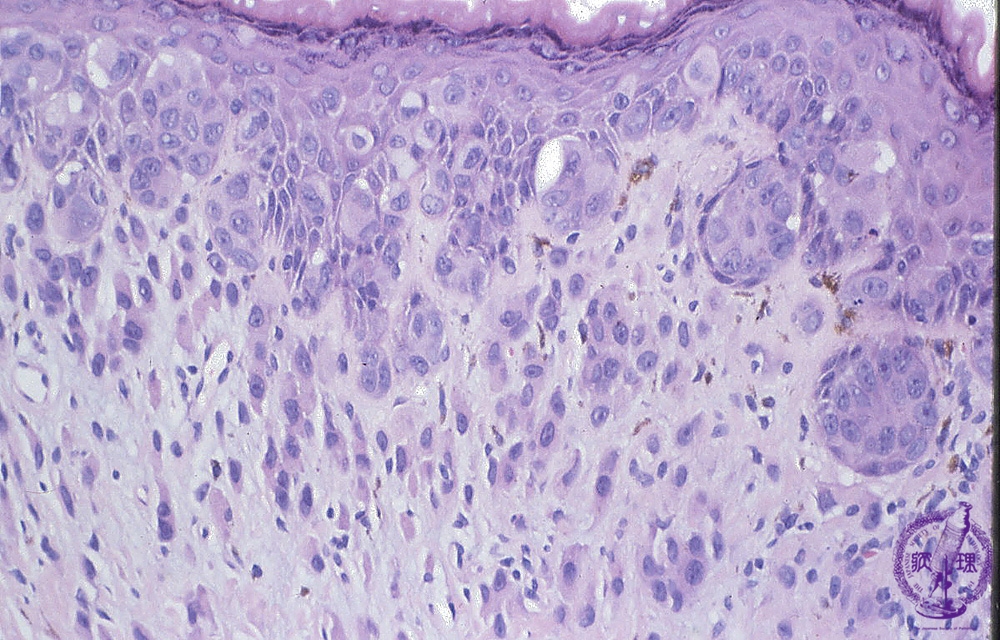

• (9)Extramammary Pagetfs disease

Microscopic findings: Paget cells spread within the epidermis and epithelium of the sweat ducts. Some Paget cells also invade the dermis.